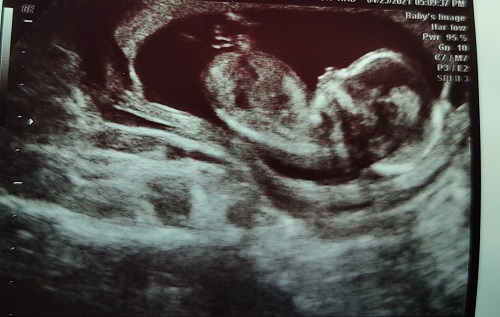

Regular ultrasounds are cool enough. We tried to get a 3-D shot of Ella, but she kept putting her hands in front of her face. We never really got a full face shot of her. Check out what we saw today…

It’s a little blurry, but there is the baby, looking right at us! WOW!